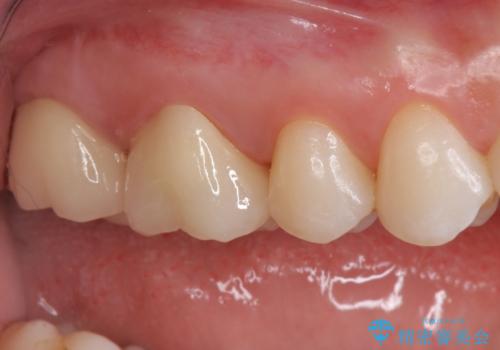

- 銀歯を白くしたいとのことで来院されました。

詰め物が覆っている面積が大きいため、強度を考慮してセラミックインレーではなくクラウンでの修復処置を進めていきます。

奥歯で咬合力の負担を考慮した結果、インレーやアンレーではなくクラウンをおすすめする場合があります。